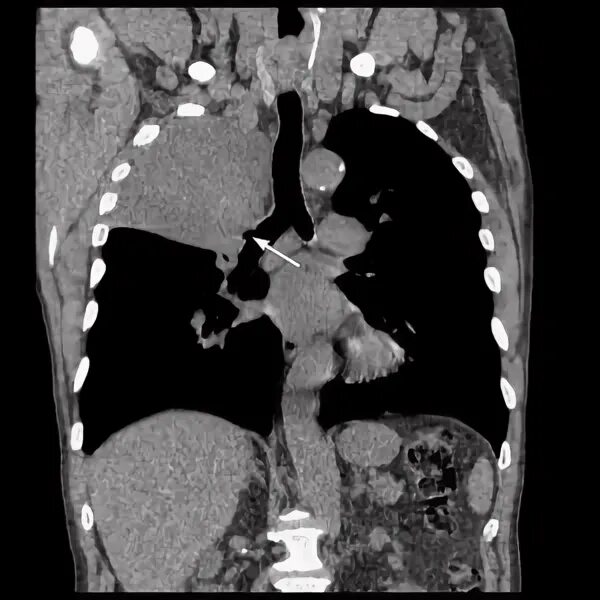

Метастазы в легких терапия